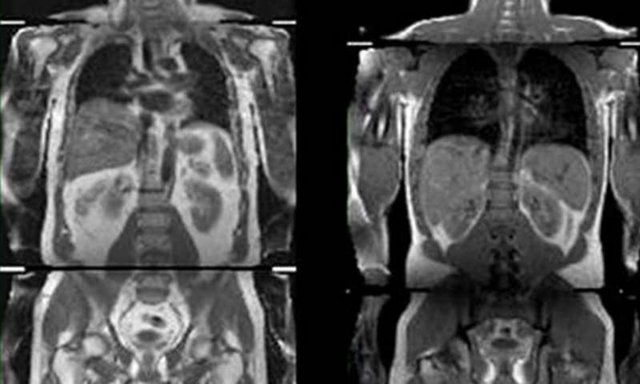

پژوهشگران، دادههای مربوط به بیش از ۵۰۰ هزار نفر که سن آنها بین ۳۷ تا ۷۳ سال بود، بررسی کردند. آنها برای تطبیق محل ذخیره چربی در بدن افراد، از اسکن امآرای استفاده کردند و نشانههای ابتلا به دیابت نوع دو، حمله قلبی و سکته را نیز در آنها مورد بررسی قرار دادند.

آنها ۱۴ نوع تغییر ژنتیکی در مولکول DNA افراد یافتند که علاوه بر ارتباط با شاخص توده بدنی آنها، با خطر ابتلا به دیابت، فشار خون و بیماری قلبی در ارتباط بود. این پژوهش نشان میدهد افرادی که این عوامل ژنتیکی را داشته باشند، چربی را زیر پوست ذخیره میکنند و بدین ترتیب، چربی کمتری در اندامهای بدن آنها از جمله کبد، پانکراس و کلیهها ذخیره میشود.